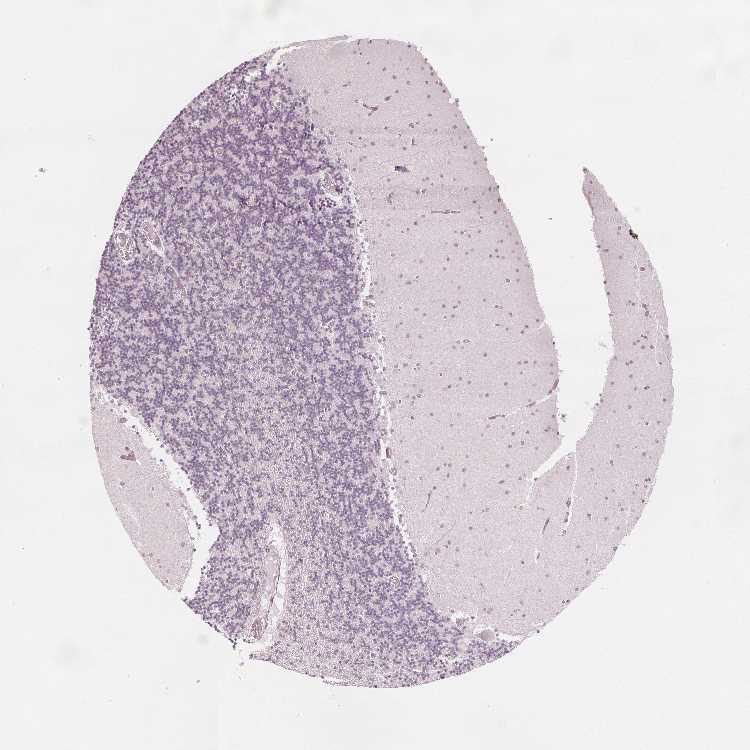

BRAIN CEREBELLUM Show tissue menu

CEREBELLUM - Expression summary

CEREBELLUM - Antibody stainingi

Antibody staining in the annotated cell types in the current human tissue is reported as not detected, low, medium, or high, based on conventional immunohistochemistry profiling in selected tissues. This score is based on the combination of the staining intensity and fraction of stained cells.

Each image is clickable and will lead to virtual microscopy that enables deeper exploration of all samples and also displays staining intensity scores, fraction scores and subcellular localization as well as patient and tissue information for each sample.

Antibody HPA049133

Purkinje cells Not detected

Cells in granular layer Not detected

Cells in molecular layer Not detected